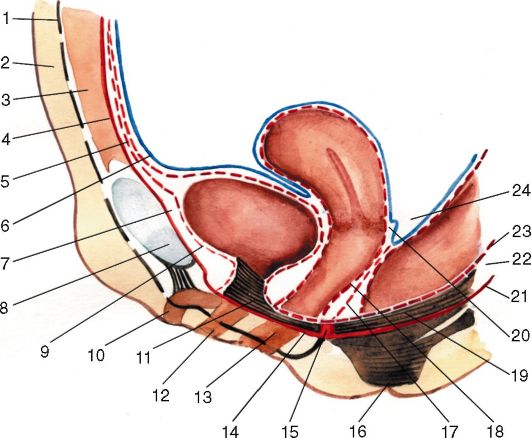

Анатомия малого таза: детальные схемы и изображения